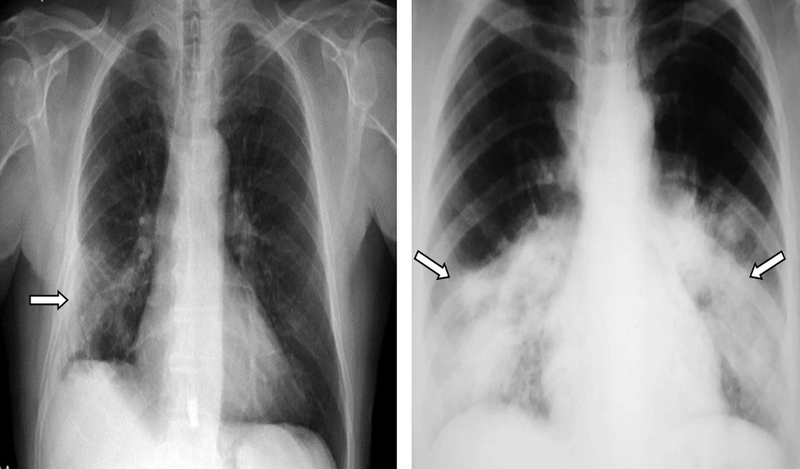

Trong hình ảnh X-quang, một trong những dấu hiệu điển hình của xơ phổi là sự xuất hiện của xơ dạng lưới hoặc dạng tổ ong. Những mô sẹo này hình thành tại nhu mô phổi dẫn đến sự thay đổi hình dạng của phổi và giảm khả năng trao đổi khí. Hình ảnh tổ ong thể hiện các vùng phổi bị tổn thương với các khoang trống hoặc không đều, do sự xơ hóa gây ra. Điều này thường báo hiệu sự tiến triển của bệnh xơ phổi khiến việc phát hiện và điều trị sớm trở nên vô cùng quan trọng.

Kết quả của một bức ảnh X-quang có thể cho thấy nhiều dấu hiệu bất thường từ những tổn thương nhỏ đến những vấn đề nghiêm trọng. Đối với bệnh nhân bị xơ phổi kết quả X-quang có thể bao gồm các đặc điểm sau: